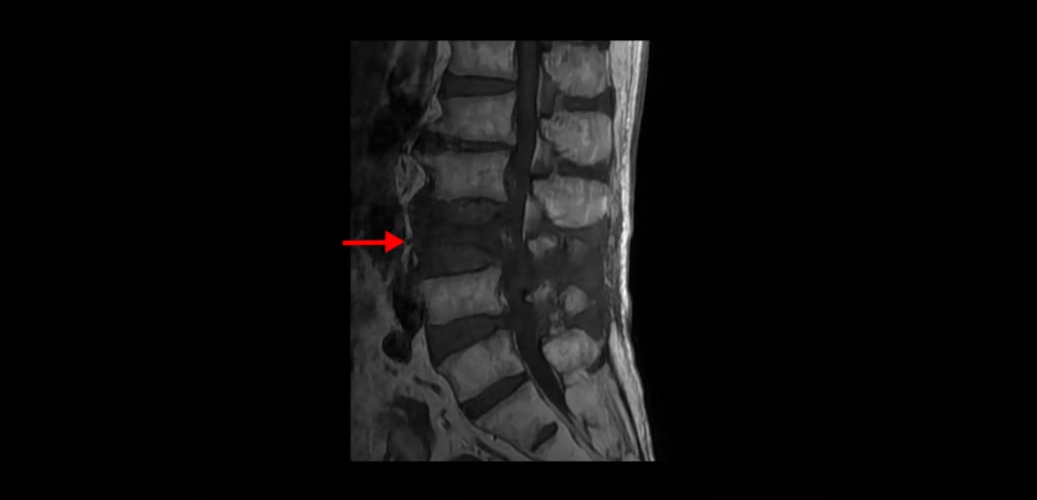

이분 MRI를 보시면 4번 5번과 5번 1번에 협착증수술, 즉 감압술을 한 흔적이 보입니다.

두꺼워진 황색인대를 제거해서 척추관의 공간을 넓힌 것으로 보입니다. 이렇게 수술했어도 신경가지가 척추 좌우로 빠져나가는 추간공은 여전히 노화와 퇴행으로 인해 좁아져 있는 상태입니다.

이런 상태에서 척추가 충격을 받으면 협착증 증상이 심해질 수 있습니다. 이분도 협착증 수술 후에 집에서 넘어지신 후 그 충격으로 척추에 압박골절이 발생하면서 심한 허리 통증이 생기고 동시에 엉덩이와 다리의 협착증 증상이 수술 전보다도 훨씬 더 심해집니다. 그래서 환자분 표현으로는 이제 못 걷게 됐구나라고 생각하셨다고 합니다.